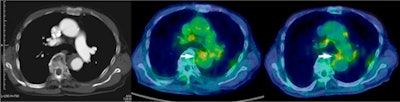

| Above: Enhanced CT (left) shows acute aortic dissection consistent with low uptake of FDG in intramural hematoma lesion on transaxial PET/CT at 50 minutes (middle) and 100 minutes (right). This 82-year-old woman experienced acute aortic dissection regression two months after onset but had a favorable outcome. Below: Enhanced CT (left) shows acute aortic dissection consistent with high uptake of FDG in dissected aortic wall on transaxial PET/CT at 50 minutes (middle) and 100 minutes (right). This 44-year-old man underwent elective repair of aortic aneurysm because of acute aortic dissection progression three months after onset and experienced an unfavorable outcome. Images courtesy of JNM. |